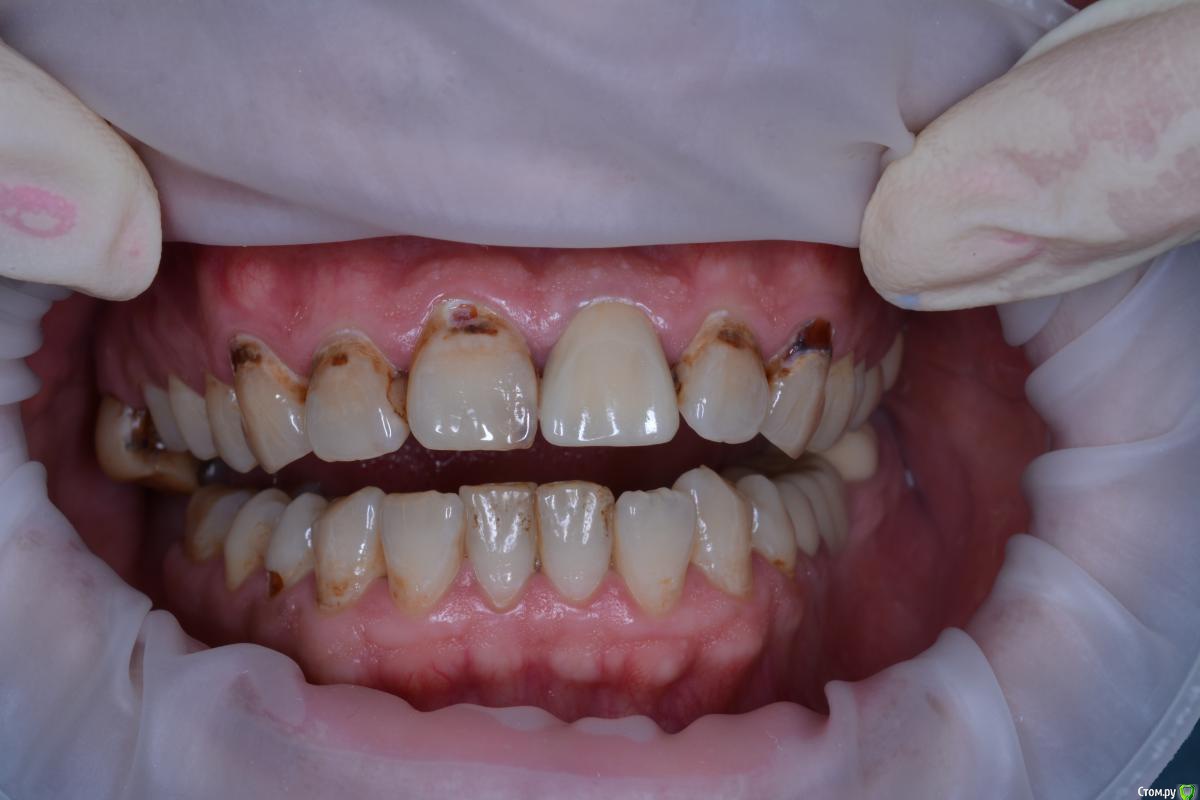

alekcandr ovs. Опубликовано 3 июля, 2017 Поделиться Опубликовано 3 июля, 2017 Планируется протезирование от 13---23 Получиться ли перекрыть цвет E.max??? может диоксид с нанесением??? Ссылка на комментарий

DR.P Опубликовано 3 июля, 2017 Поделиться Опубликовано 3 июля, 2017 (изменено) Сейчас, выполняю похожее лечение. Пролечил кариес этих флюорозных эрозий. Оттенок в тон культей. Все делал с коффердамом, получается ретракция платком и полное обнажение границ эрозий. Получилось отлично. После уже препарирование. Я выбрал виниры на рефракторе...но это потому что люблю его больше. Но так же можно сделать и на имаксе, думаю MO будет достаточно Изменено 3 июля, 2017 пользователем DR.P Ссылка на комментарий

alekcandr ovs. Опубликовано 8 июля, 2017 Автор Поделиться Опубликовано 8 июля, 2017 Сейчас, выполняю похожее лечение. Пролечил кариес этих флюорозных эрозий. Оттенок в тон культей. Все делал с коффердамом, получается ретракция платком и полное обнажение границ эрозий. Получилось отлично. После уже препарирование. Я выбрал виниры на рефракторе...но это потому что люблю его больше. Но так же можно сделать и на имаксе, думаю MO будет достаточноспасибо!!! Пошел Вашим путем,немного запарился с платком от коффера,очень он не хотел полностью отдавливать десну.Вы какие платки используете??? Ссылка на комментарий